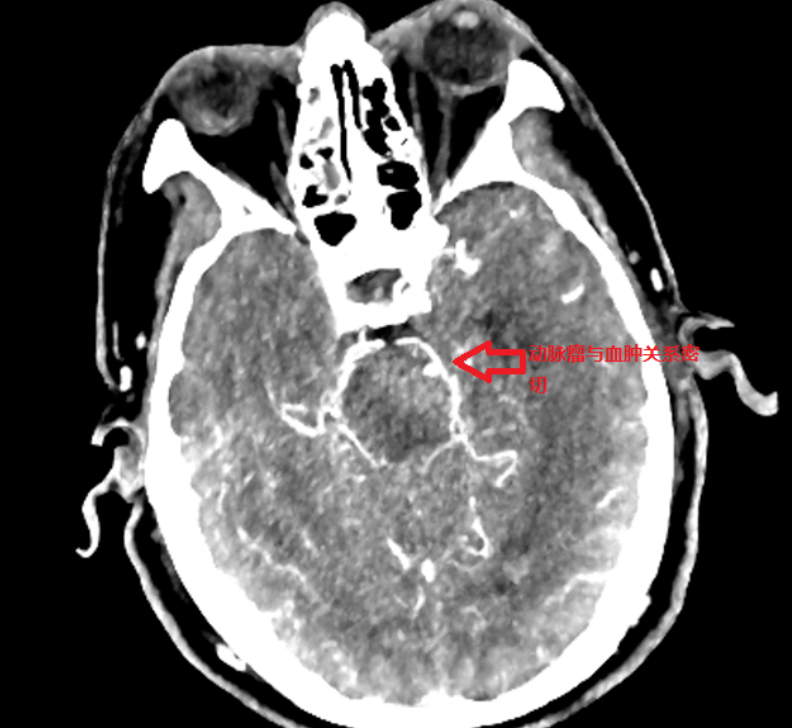

??入院后,为明确孙先生多次脑出血的原因,复查颅脑CT并急查颅脑动脉CT血管成像,显示其左侧大脑后动脉P2段有动脉瘤,且动脉瘤已破裂并破入脑干,左侧基底节出血,出血量约为30毫升,情况十分危急。

??术前颅脑CT

??颅脑CTA原始图像示动脉瘤与血肿关系密切